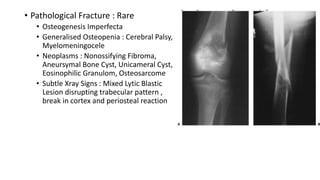

• Pathological Fracture : Rare

• Osteogenesis Imperfecta

• Generalised Osteopenia : Cerebral Palsy,

Myelomeningocele

• Neoplasms : Nonossifying Fibroma,

Aneursymal Bone Cyst, Unicameral Cyst,

Eosinophilic Granulom, Osteosarcome

• Subtle Xray Signs : Mixed Lytic Blastic

Lesion disrupting trabecular pattern ,

break in cortex and periosteal reaction